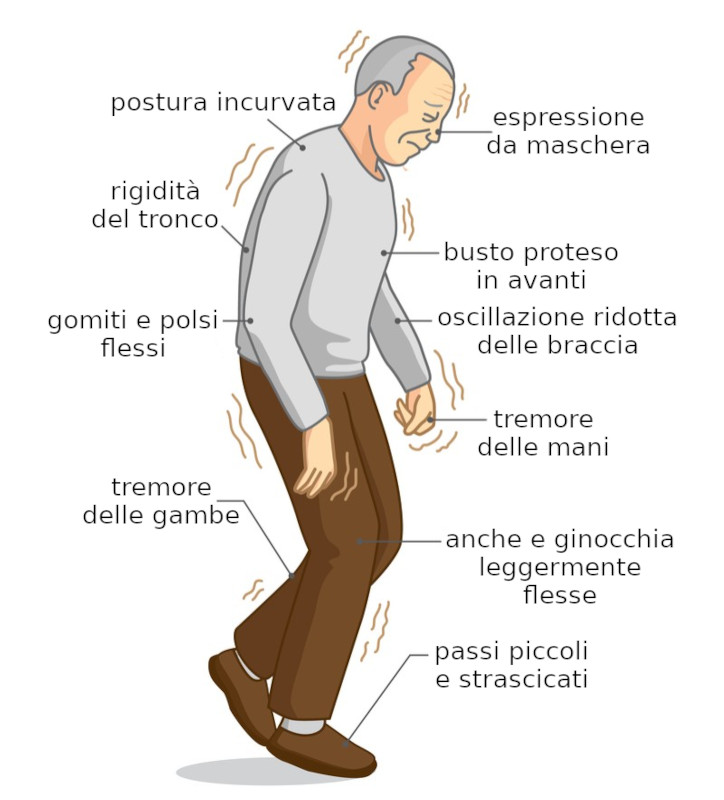

La Malattia di Parkinson (MD) è una malattia degenerativa cronica del sistema nervoso centrale che colpisce principalmente il sistema motorio. La comparsa dei sintomi è graduale e riguardano la funzione motoria, ma generalmente con l'avanzare del tempo, possono comparire sintomi non motori che poi divengono quelli più invalidanti. Per la maggioranza dei casi la sintomatologia esordisce con un tremore leggero di uno o due arti, poi compare una certa rigidità del movimento e della struttura corporea, i movimenti tendono a rallentare ed il camminare diventa incerto e difficile.

I sintomi caratteristici della malattia sono quattro, sebbene se ne aggiungano altri a conferma della diagnosi:- Tremore: che consiste in tremore lento della mano a riposo, ma che scompare durante il movimento volontario e nelle fasi REM del sonno. Generalmente compare in una sola mano, ma con il passare del tempo, in assenza di trattamenti, coinvolge anche l'altra mano. Il movimento tipico è quello di arrotolare le pillole o di contare i soldi, che viene eseguito da indice e pollice.

- Lentezza del movimento: si osserva in ogni caso ed è causata da disturbi nella pianificazione motoria e di inizializzazione del movimento, sebbene l'intero processo motorio appaia alterato. Il movimento coordinato e simultaneo è compromesso. L'invalidità che ne deriva è elevata e ogni funzione di base ne risulta alterata, come il vestirsi, il mangiare, il lavarsi. La persona non riesce a fare due movimenti contemporaneamente e questo genera stizza e frustrazione, il che peggiora ulteriormente la situazione. Paradossalmente la persona riesce ad andare in bicicletta o salire le scale con semplicità.

- Rigidità: La resistenza al movimento degli arti causata da un aumento del tono muscolare, causa una rigidità motoria. Si verifica il fenomeno della "rigidità a ruota dentata". Può essere associata a dolori articolari ed è spesso asimmetrica, colpendo i muscoli del collo e delle spalle prima dei muscoli del viso e delle estremità. L'avanzare del disturbo porta solitamente ad un irrigidimento di tutto il corpo.

- Instabilità posturale: Si manifesta con perdite di equilibrio e cadute ripetute, con o senza fratture ossee